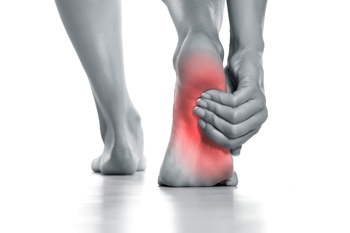

Reasons for Nighttime Foot Pain

Foot pain may affect the toes, arches, heels, or ankles, and it often becomes more noticeable at night, when the body is at rest. Muscle fatigue from standing or walking for long periods of time, can cause cramps that worsen during sleep. Plantar fasciitis, an inflammation of the tissue that supports the arch, may lead to sharp or throbbing heel pain that persists into the night. Nerve conditions such as Morton’s neuroma or peripheral neuropathy can create burning, tingling, or stabbing pain that interrupts sleep. Circulation problems related to diabetes may also produce aching or cramping when blood flow to the feet is reduced. In some cases, sciatica can cause pain that radiates down into the feet, making nighttime discomfort worse. A podiatrist can determine the source of the foot pain and provide treatment to relieve symptoms and protect long-term foot health. If you frequently experience nighttime foot pain, it is suggested that you schedule an appointment with a podiatrist for an exam and appropriate treatment solutions.